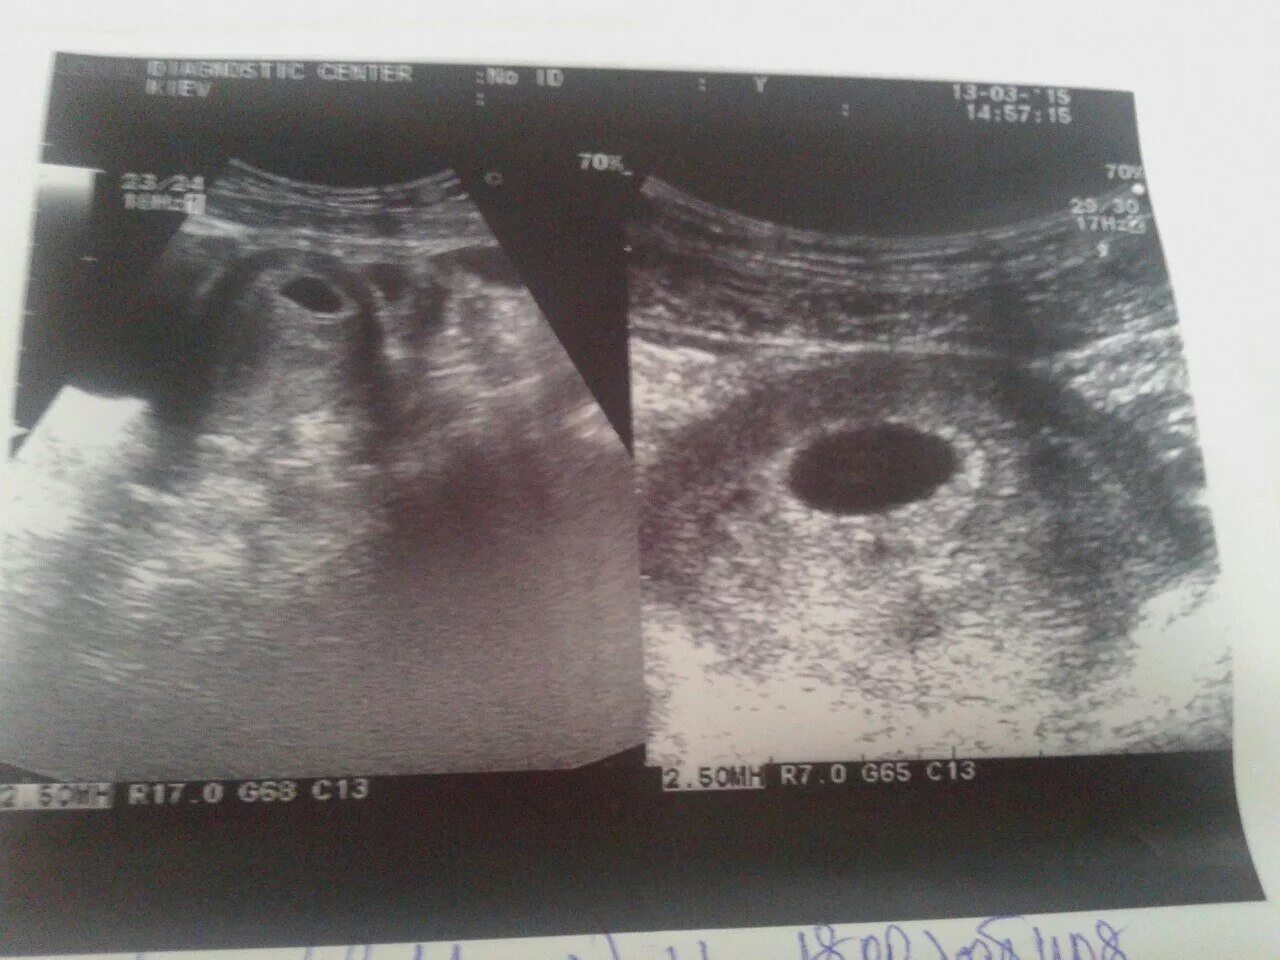

Желточный мешок 2 мм